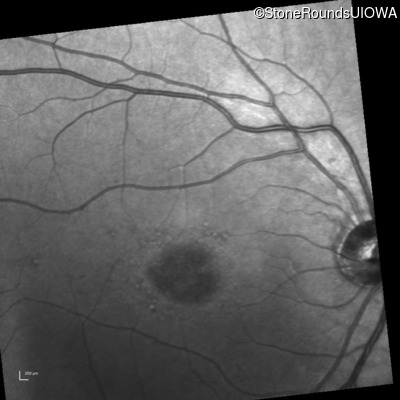

Infrared Fundus Photograph - Right - 20/80 -1

Exemplar

Infrared Fundus Photograph - Left - 20/80